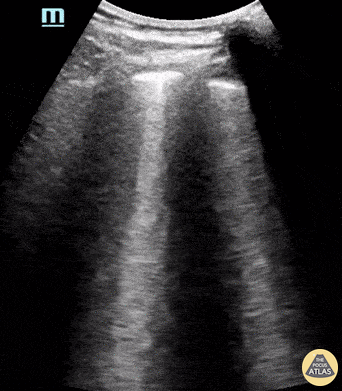

14 year-old female known to be SARS-CoV-2 positive presented with chest pain and shortness of breath. POCUS revealed findings consistent with COVID pneumonia including thickened pleura and presence of multiple B-lines. Paul Khalil, MD. Assistant PEM POCUS director at University of Louisville/Norton Children’s @khalil3paul